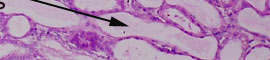

At medium power, pale pink protein casts are visible in the lumina of the tubules. Tubules with enlarged lumina and flattened lining epithelium such as these are described as atrophic.